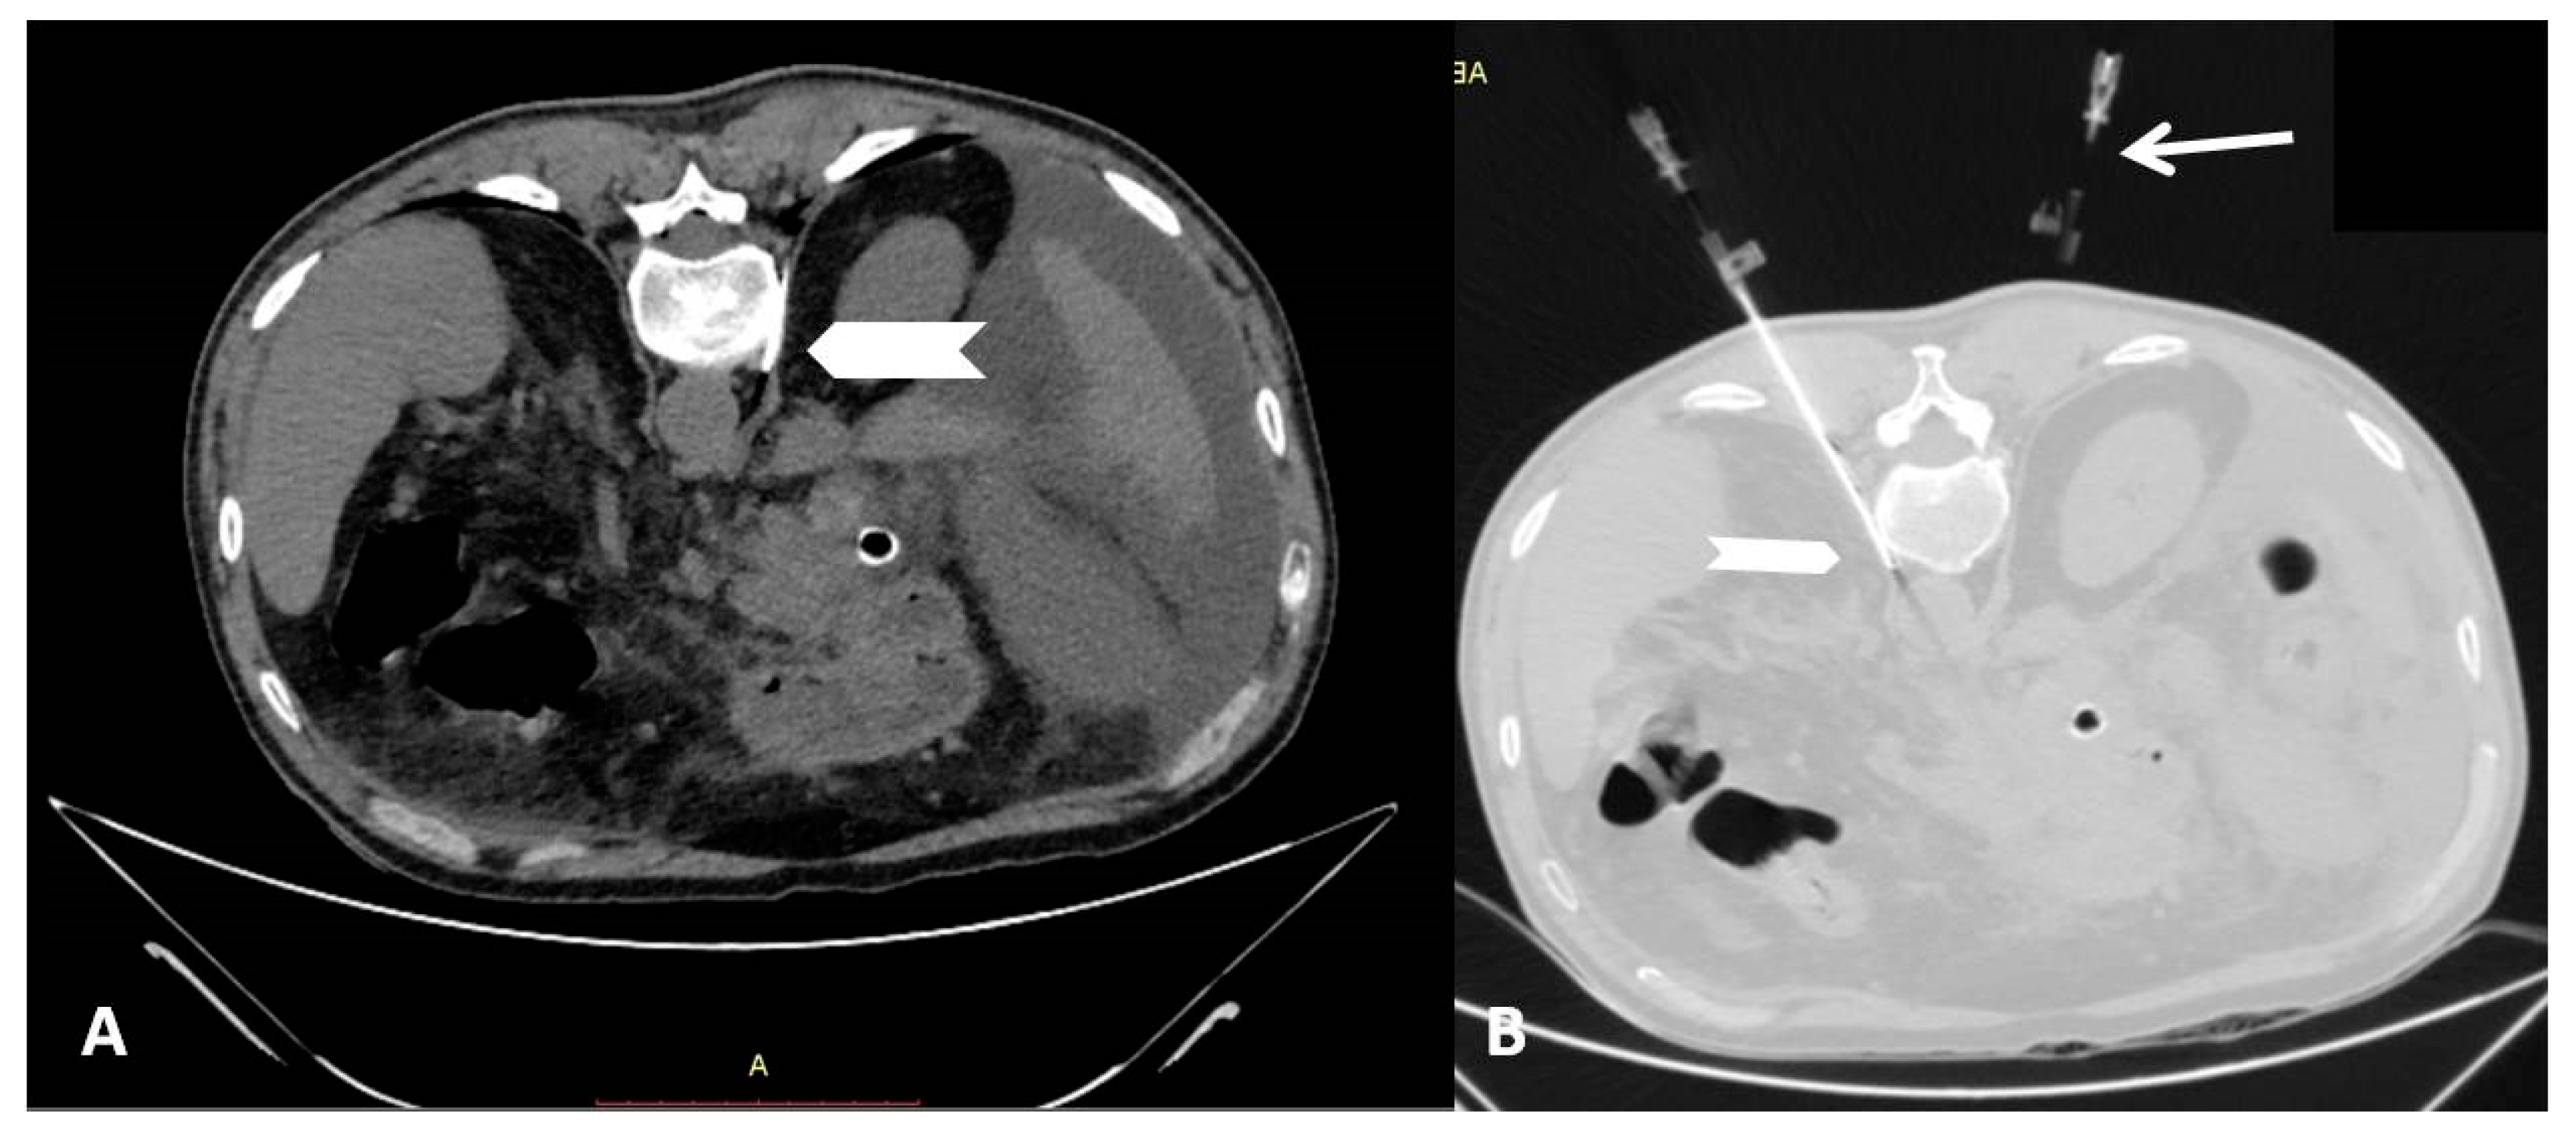

2.2. Percutaneous Radiofrequency Neurolysis